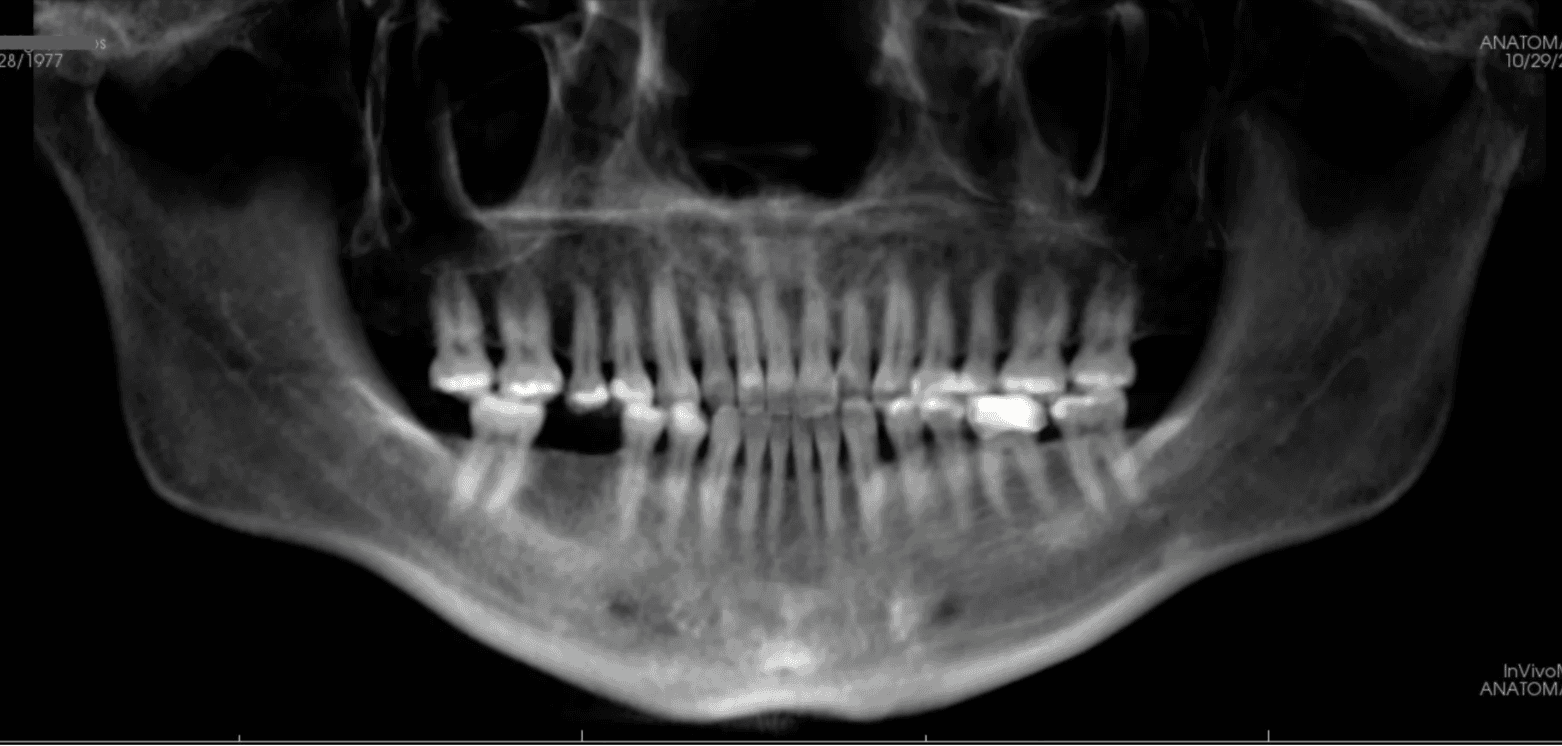

Initial treatment

X-RAYS